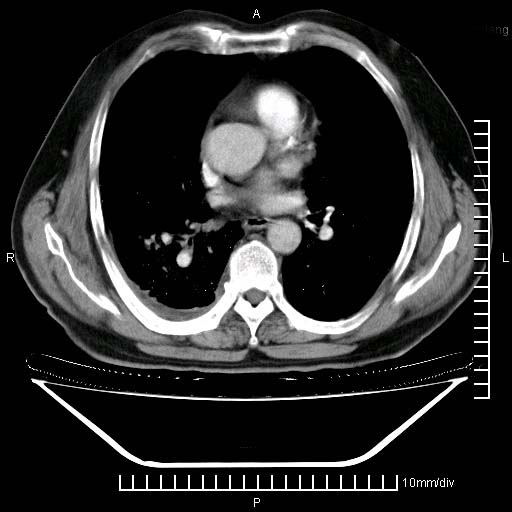

既往肺结核,近10几天,咳嗽,咳痰,右侧胸痛,疼痛较明显,右上肺斑块考虑结核灶胸膜粘连,增强,可惜动脉期没有定好,未见强化,可延迟4分后又见较明显强化,中心见低密度影,如果说结核是边缘强化,可这个灶强化的面积挺大的,让人很挠头。

1)两肺继发性肺结核。2)右侧胸膜增厚+少量胸腔积液。